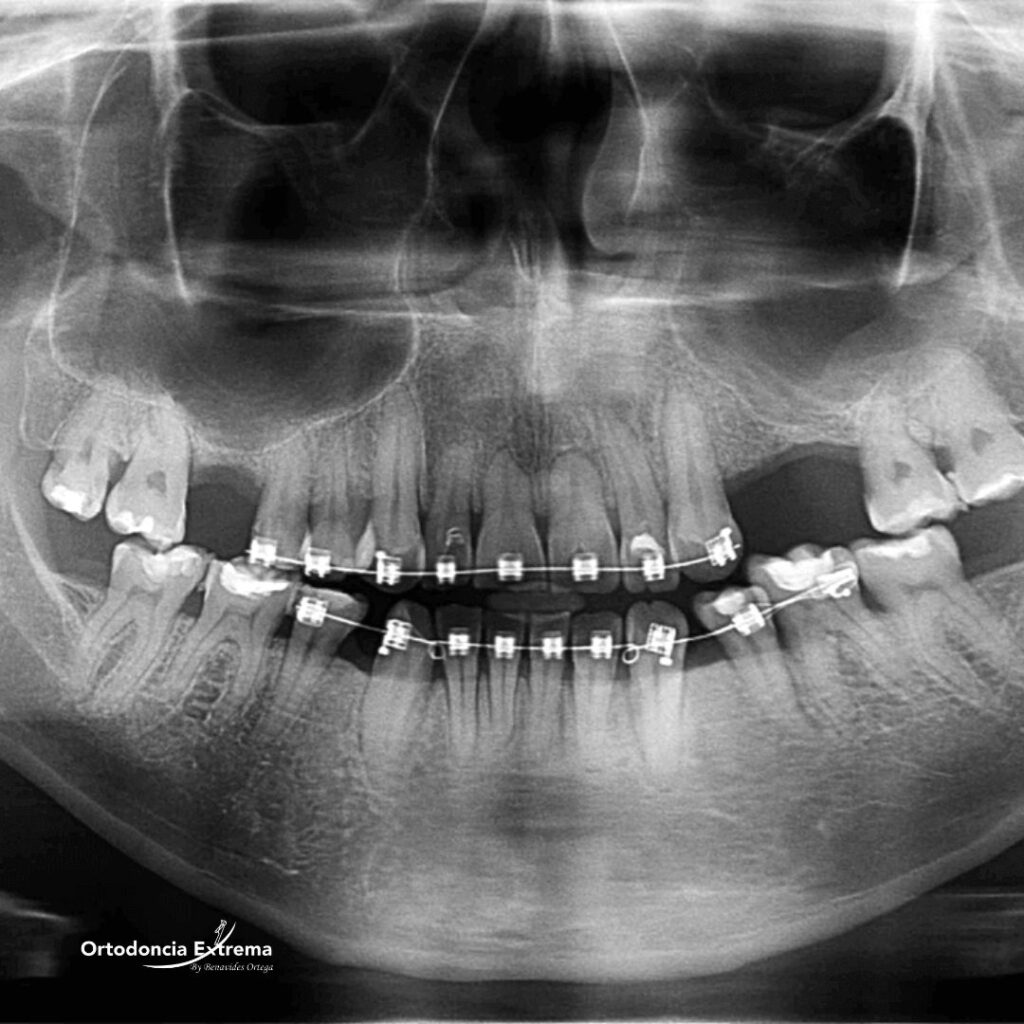

La ortodoncia no es colocar brackets. Es una especialidad compleja de arquitectura y biología. La causa #1 de los tratamientos fallidos es la falta de especialización y de un diagnóstico preciso.

Mientras otros ponen “brackets sin control”, nosotros escaneamos digitalmente tu mordida en 3D. No adivinamos, planificamos.

Este mapa digital nos permite diseñar la posición final de cada diente y prevenir la desadaptación de la mordida y los dolores articulares antes de que ocurran. Protegemos tus raíces con movimientos calculados milimétricamente